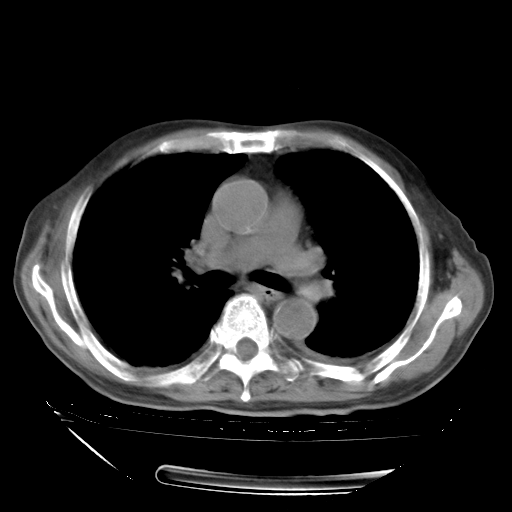

甲强龙80mg/日+抗结核治疗(异烟肼+利福霉素+乙胺丁醇)10天。复查肺部CT。

治疗10天肺部CT

补充下:5月9日胸部CT:似乎已见双下肺胸腔积液了,鉴于目前有下肢水肿,肝功示:白蛋白低,应注意多浆膜腔积液(漏出液可能大?),需注意!